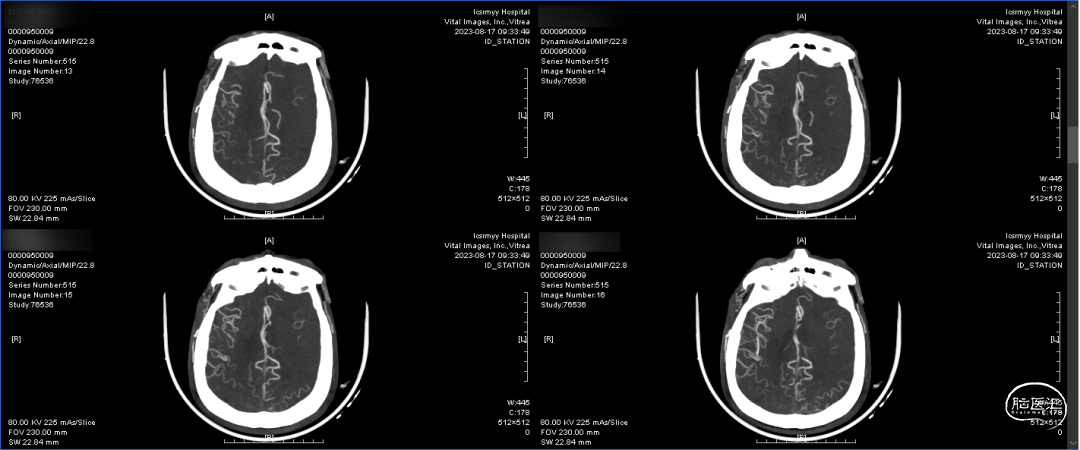

术前CTA:双侧颈内动脉闭塞,代偿可。

术前CTA:颅内代偿可。